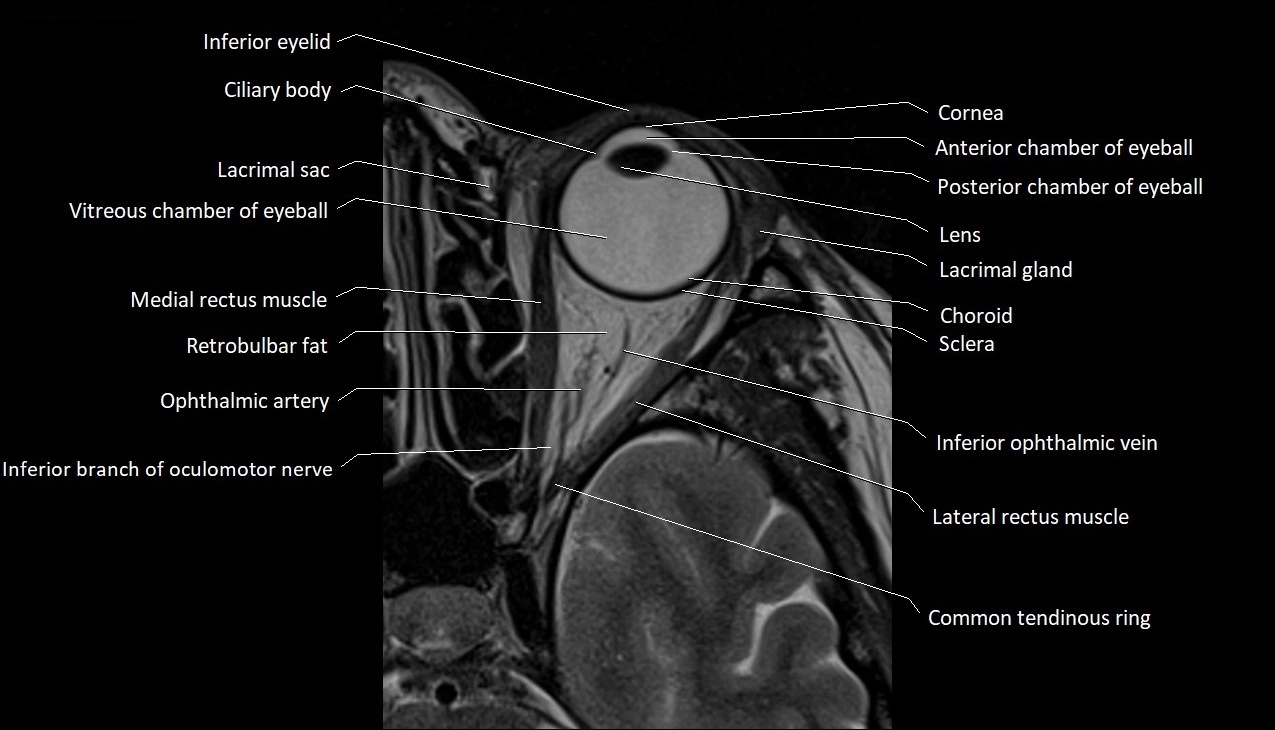

- Anterior chamber of eyeball

- Choroid

- Cornea

- Inferior eyelid

- Lacrimal gland

- Lateral rectus muscle

- Medial rectus muscle

- Oculomotor nerve (inferior branch)

- Orbital part of optic nerve

- Posterior chamber of eyeball

- Retrobulbar fat

- Sclera

- Superior ophthalmic vein

- Vitreous chamber of eyeball